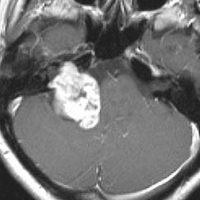

聴神経腫瘍でまず手術が必要なのは巨大なものです。この4枚の写真は私が実際に手術をした患者さんのものです。脳幹部という脳の最も大切なところが腫瘍によって圧迫されて変形しているのが特徴です。右上のものはのう胞性腫瘍なので大きさの割に手術のリスクは高くありませんが,左上のものは実質性で出血性のものですごくリスクが高い手術でした。左下のものは普通のリスク。右下のものは超高難易度のものです。